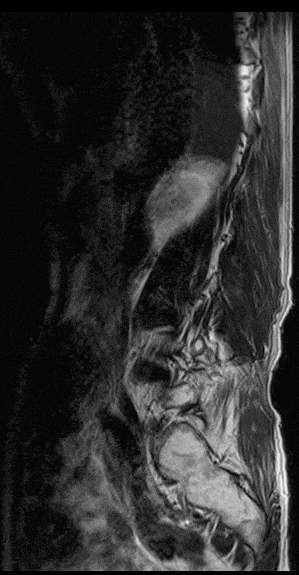

在磁共振领域,深度学习技术对图像进行降噪、上采样、减轻振铃伪影的处理,带来了清晰且细节丰富的图像。

过去,高分辨率图像的获取往往伴随着漫长的扫描时间,这影响了图像获取的效率,对于危重疾病的快速诊断是一大挑战。然而,PIQE技术的出现彻底颠覆了这一局面。此次发布的全新3T磁共振Galan Supreme,搭载全新的自研磁体和梯度线圈,并深度融合PIQE技术,可以实现在不增加扫描时间的前提下,轻松获取到高分辨率的图像,为临床带来了兼具高效与高质量的影像体验。